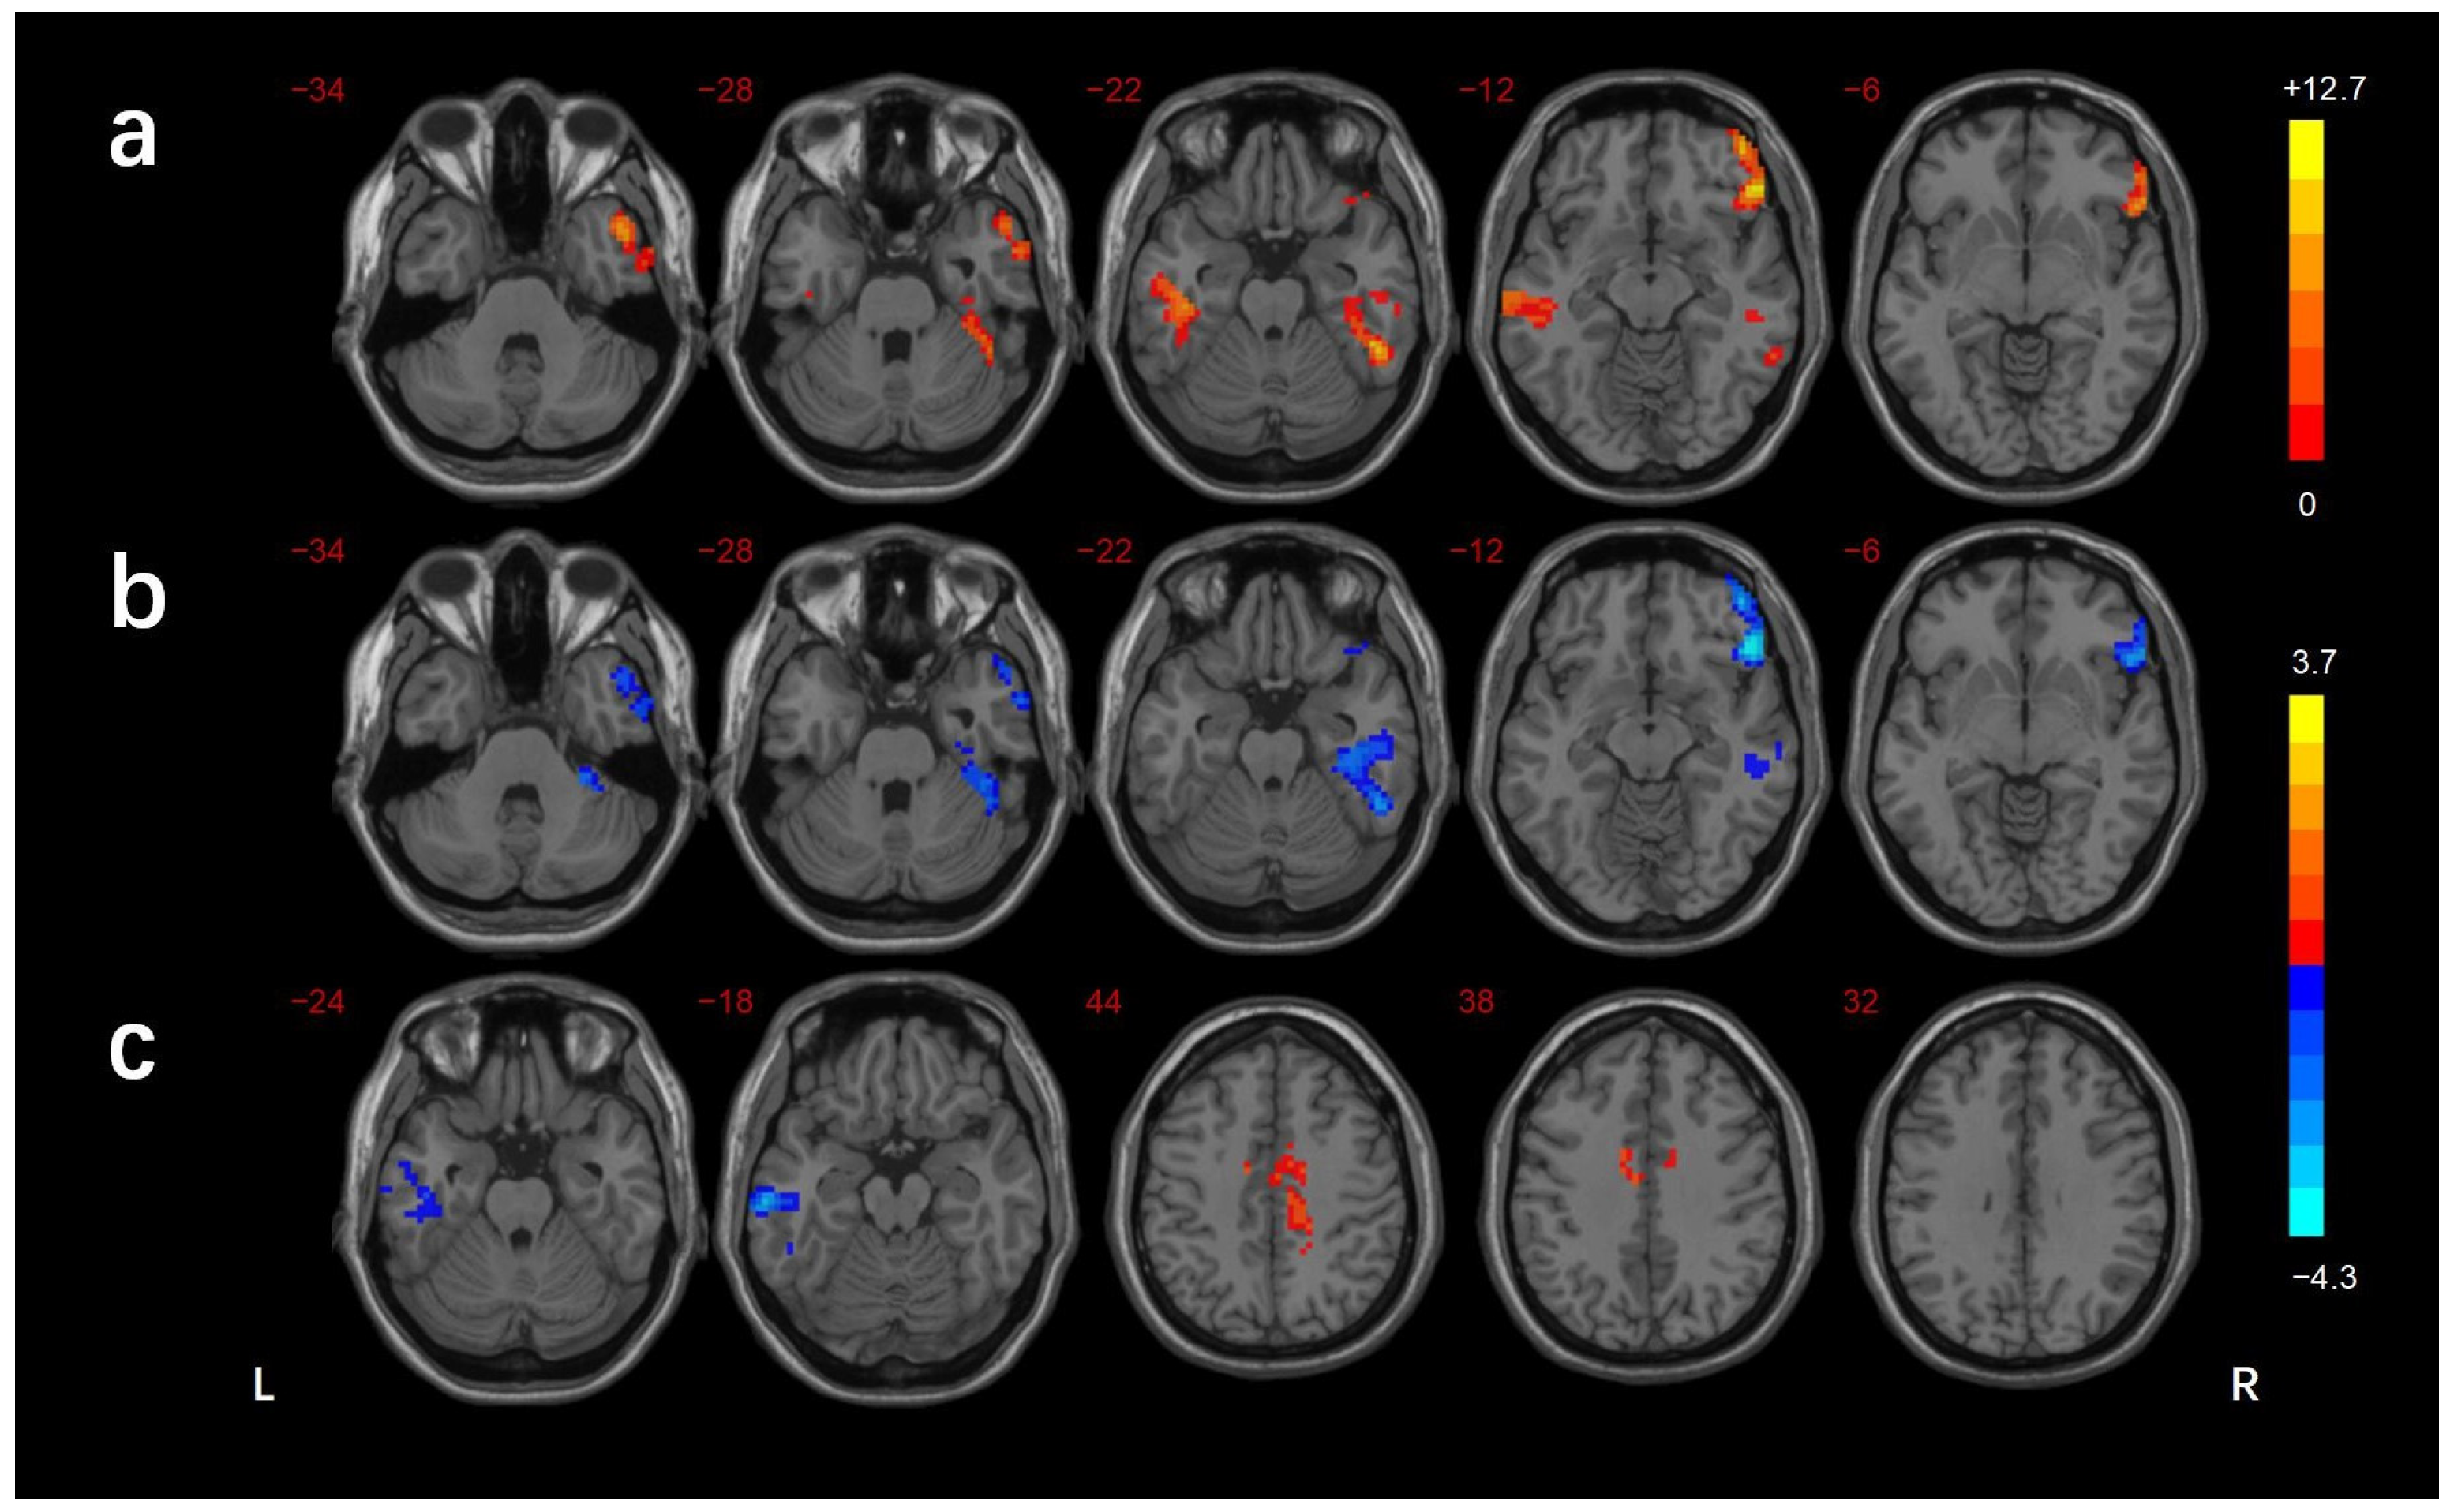

3.2. FCD Analysis

| Brain Regions | BA | Voxels (mm3) | Peak MNI Coordinates | f/t-Value | ||

|---|---|---|---|---|---|---|

| X | Y | Z | ||||

| ANOVA | ||||||

| R_MTG/ITG | 21/38 | 194 | 51 | 9 | −39 | 10.514 |

| R_MTG/ITG/FG/cerebellar lobule VI | 37/20 | 187 | 54 | −48 | −18 | 11.278 |

| L_ITG | 21 | 155 | −60 | −21 | −15 | 10.434 |

| R_IFG | 47 | 206 | 51 | 33 | −15 | 12.651 |

| DMCN vs. HC | ||||||

| L_MTG/ITG | 21 | 188 | −66 | −24 | −15 | −3.975 |

| B_MCC/R_precuneus | 24 | 188 | 15 | −24 | 42 | 3.665 |

| DMCI vs. HC | ||||||

| R_MTG/ITG | 21/38 | 185 | 51 | 12 | −45 | −4.018 |

| R_MTG/FG/cerebellar lobule VI | 37/20 | 299 | 39 | −24 | −18 | −3.908 |

| R_IFG | 47 | 229 | 48 | 30 | −12 | −4.243 |